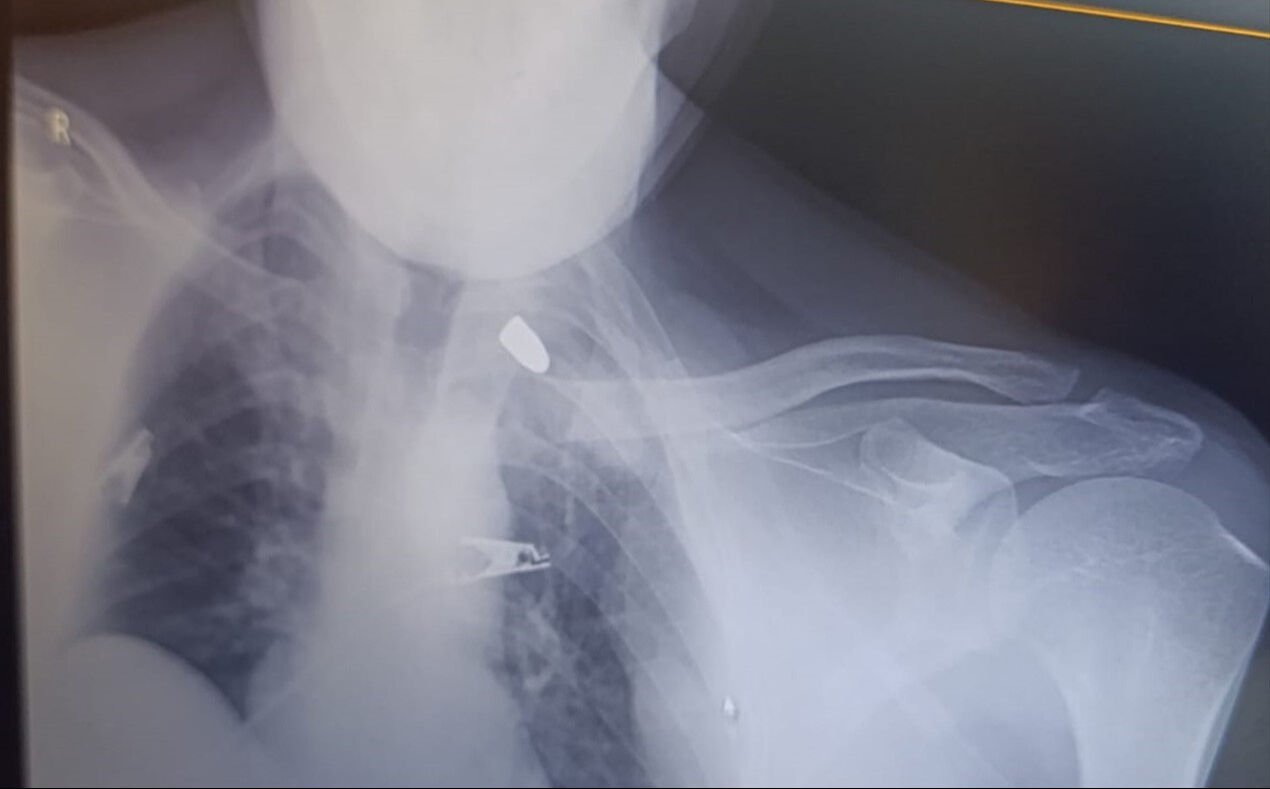

Göğsüne isabet eden mermi ile yaralanan Ataş kanlar içerisinde kaldı. Olayı fark eden yakınlarının ihbarı üzerine Ataş, hastaneye kaldırıldı.

Tedavisi devam eden adama isabet eden kurşunun göğsünde takılı kaldığı görüldü. Polis silahı ateşleyen kişinin tespit edilmesi için çalışma başlattı.